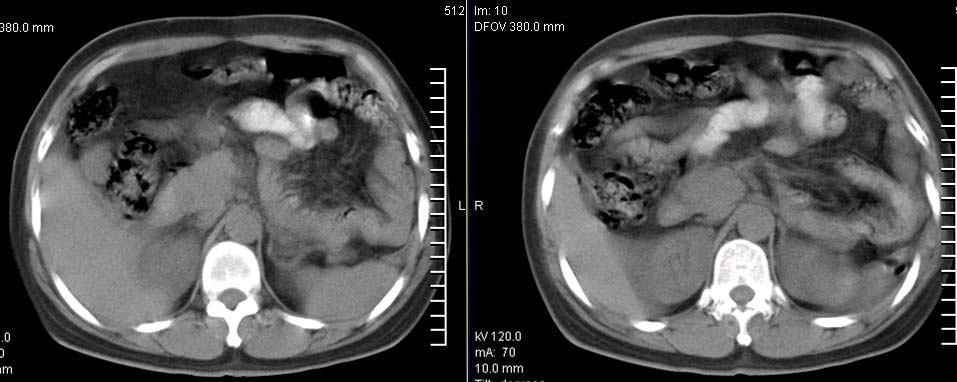

标题: CT9722:卵巢巨大占位,约10*18*21CM大小 [打印本页]

标题: CT9722:卵巢巨大占位,约10*18*21CM大小

卵巢巨大占位,约10*18*21cm大小

考虑来源于卵巢的巨大占位,良性可能性大,内可见坏死区,建议强化检查。

囊腺瘤不管是浆液性,还是黏液性的,液体成分应该占的比例很大吧!!这个病灶其实是个实性肿块,更看不到囊腺瘤所能见到的分隔??请笔者提供ct值?望大家再仔细分析??

右侧卵巢的巨大占位,病灶大部分呈实性,以恶性可能大。

右侧附件区巨大囊性肿块,边缘光滑,密度较高,左侧缘由多个低密度区,首先考虑囊腺瘤可能。